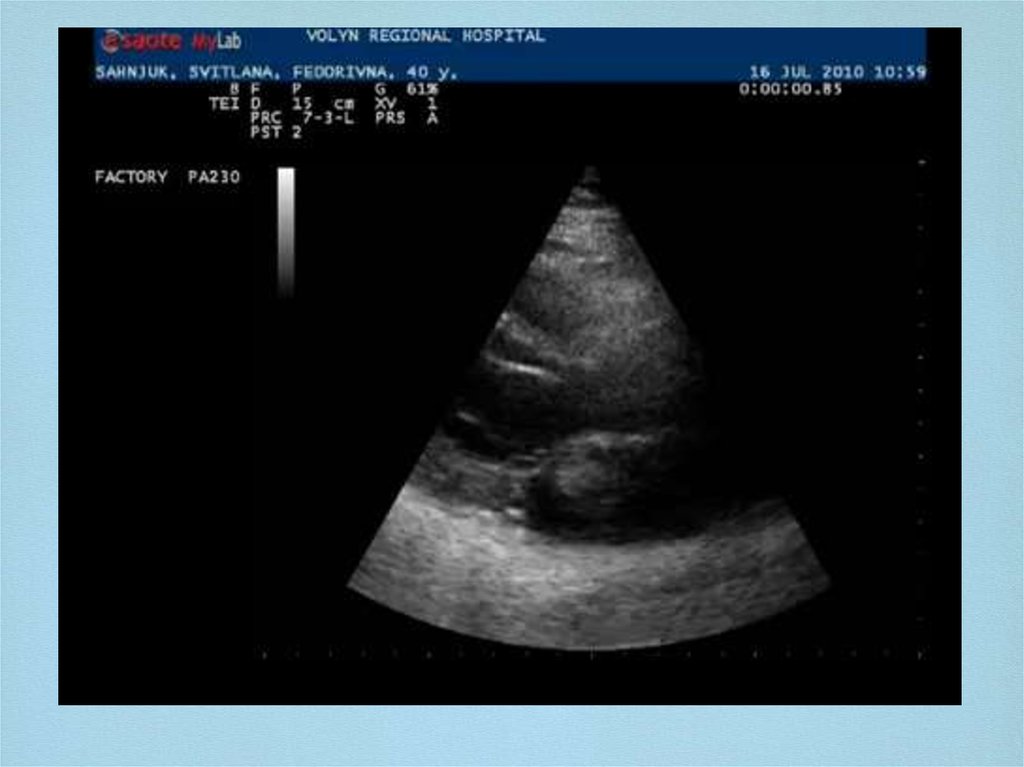

Ехокардіографія

11. Ехокардіографія